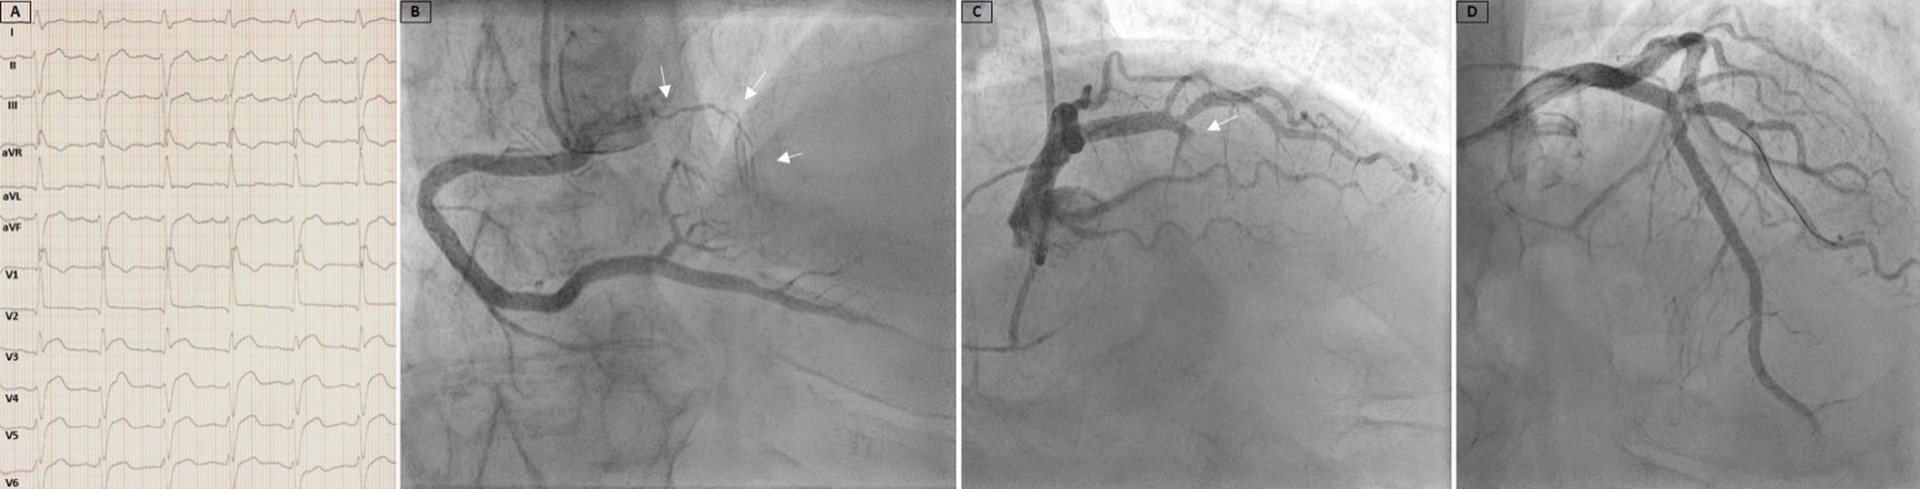

A 71-year-old man with a medical history of diabetes, hypertension, and smoking presented to the emergency department because of acute retrosternal pain. An electrocardiogram (ECG) recorded left anterior fascicular block, right bundle branch block, and ST-segment elevation in leads V3 to V5 without reciprocal changes (Figure A). Urgent coronary angiography demonstrated a descending septal artery, also known as Bonapace’s branch, arising from the proximal right coronary artery (Figure B, Video 1), and a totally occluded left anterior descending artery (LAD) in the mid-segment (Figure C, Video 2).

The occlusion was treated with implantation of a drug-eluting stent, resulting in a good angiographic result (Figure D, Video 3). The echocardiogram showed preserved ejection fraction (EF) and only moderate elevation of high-sensitivity troponin (hsTn) (hsTn-max: 9129; normal: < 34.2). The clinical course was uneventful, and the patient was discharged in good condition.

Bonapace’s branch, though an infrequent anatomical variation, provides valuable collateral circulation to the interventricular septum, atrioventricular node, and His bundle during acute or chronic occlusion of the LAD, especially in the absence of a well-developed first septal branch. In our patient, collateral blood supply through Bonapace’s branch to the acutely occluded LAD reduced the ischemic consequences, as shown by the absence of reciprocal ECG changes, moderate elevation in hsTn, and preserved EF at discharge.